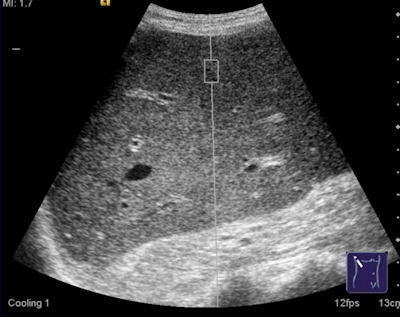

The technique uses high-energy, focused acoustic pulses and conventional diagnostic sonography methods to measure tissue elasticity. An acoustic "push" pulse is produced by the ultrasound probe and generates shear waves that are propagated into the liver. Using image-based localization and proprietary implementation of ARFI technology, shear-wave speed may be quantified and, in precise anatomical regions, focused on a region of interest, with a predefined size provided by the system.

The force impulse causes displacement of the tissue, and the time scale of this response is much slower than that of the acoustic propagation. The interaction of sound with tissue can be used to receive additional information about the diagnosed region, beyond what is normally provided in an ultrasound image. The velocity is proportional to the tissue stiffness, with faster wave progression occurring through stiffer material, and is measured in meters per second, Sporea stated.